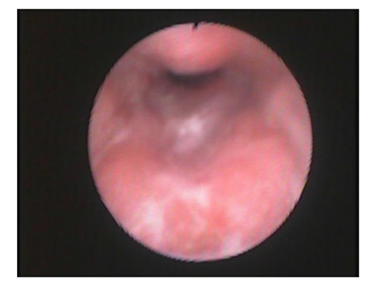

Figure 5 Anterior–posterior pattern of pharyngeal collapse in which a collapse due to anterior pharyngeal collapse against the posterior pharyngeal wall is detected (the base of the tongue against pharyngeal wall during the DISE).

2. Hypopharynx: nearly half of patients 48.5 % had concentric obstruction, 19.7 % had antero-posterior obstruction and 31.8 % had latero-lateral obstruction.